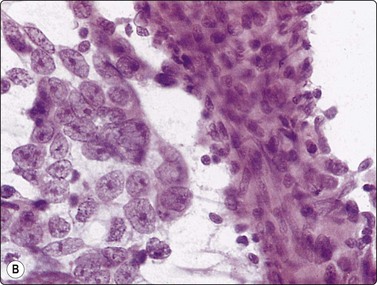

Yolk sac tumor (Figs 13.37 and 13.38)14,53-56,59-61,63

Most cytologic reports are based on FNA performed on metastatic sites. A detailed account of the morphologic spectrum of endodermal sinus tumor has been reported by Akhtar et al.53

image image

Fig. 13.37 Endodermal sinus tumor

(A) Polypoid epithelial fragment of large malignant cells with pale, almost clear, vacuolated cytoplasm (MGG, HP); (B) Corresponding tissue section (H&E, IP).

Fig. 13.38 Endodermal sinus tumor

(A) A glomeruloid cell cluster with vacuolated cytoplasm on a mucoid background (DQ, IP); (B) Cell cluster with a vascular stalk and several hyaline globules.

Criteria for diagnosis

Mucoid background,

Glomeruloid structures,

Schiller-Duval bodies (characteristic finding when present),

Very immature cells, prominent nucleolus, basophilic cytoplasm,

Small naked nuclei,

Intra- or extracellular PAS-positive hyaline globules (AFP positive),

Prominent cytoplasmic vacuoles and distinct cell boundaries confer a clear-cell appearance,

Immunocytochemistry: focal staining for AFP, AE1/AE3 and PLAP; negative for OCT image.

Pure yolk sac tumors are almost always encountered in infants and young children but rare in the first 6 months of life.49 In adults, this pattern is seen in approximately 40% of nonseminomatous GCT;12 however, it can easily be mistaken for embryonal carcinoma in FNA smears. This is why most reported cases are of metastatic tumors. Hyaline globules and eosinophilic membrane-like material are hints to the diagnosis of this tumor type (Fig. 13.38B). In infants and young children, the aforementioned cytological criteria permit a confident diagnosis by FNA.